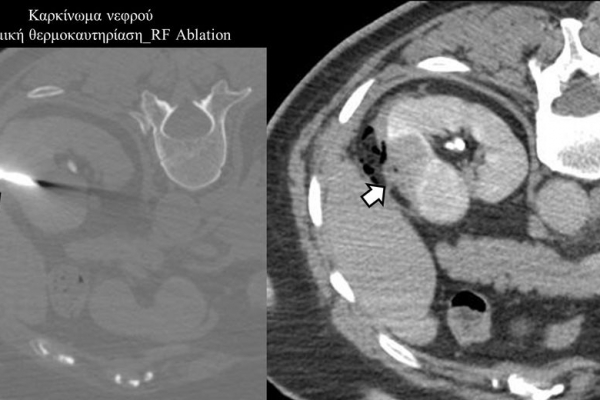

Πρόκειται για την πιο σύγχρονη τοπική θεραπεία όγκων του ήπατος, του νεφρού, του πνεύμονα, των οστών και των όγκων μαλακών μορίων. Παθοφυσιολογικά βασίζεται στην τοπική καταστροφή των καρκινικών κυττάρων με τη δημιουργία ιδιαίτερα υψηλών θερμοκρασιών εντός του όγκου. Αυτό επιτυγχάνεται με τοποθέτηση ειδικών ηλεκτροδίων εντός του όγκου υπό ακτινολογική καθοδήγηση (αξονικός τομογράφος ή υπέρηχος). Τα ηλεκτρόδια αυτά παράγουν υψηλή θερμοκρασία είτε με τη βοήθεια ραδιοσυχνοτήτων (RFablation), είτε με τη βοήθεια μικροκυμάτων (MWablation) και προκαλούν πηκτική νέκρωση των καρκινικών κυττάρων χωρίς να επηρεάζουν τα φυσιολογικά κύτταρα.Το αποτέλεσμα είναι μόνιμο.